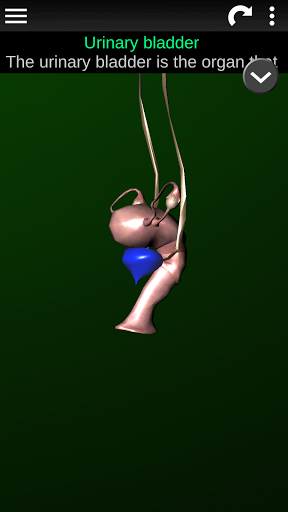

Internal Organs 3D Anatomy 3.4

Internal Organs 3D Anatomy 3.1

Organs 3D Anatomy 2.0.12